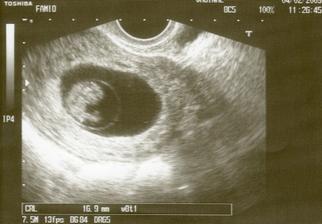

♥ 4.2.2009♥ Menší poplach, maminka trošičku špinila, takže neplanovaná kontrola a 2. UTZ. Ale vše je ok, srdíčko krásně tluče a brouček měl otevřenou pusinku 🙂